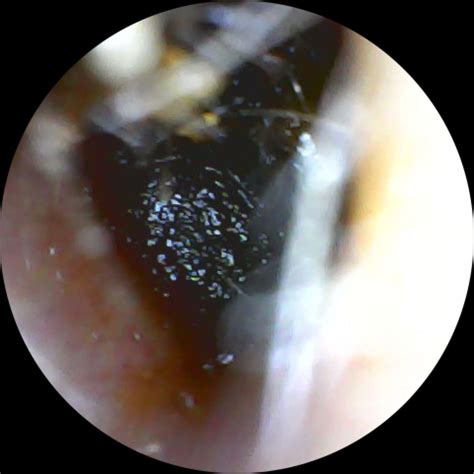

• Earwax Buildup: While often associated with dull pressure, hardened earwax can occasionally press against the eardrum, leading to sharp, stabbing sensations.

• Foreign Objects: Especially in children, small objects lodged in the ear canal can cause immediate and intense pain.

• Eardrum Perforation: A tear or hole in the eardrum—often caused by loud noises, sudden pressure changes, or inserting objects like cotton swabs too deeply—is frequently associated with sudden, sharp pain.